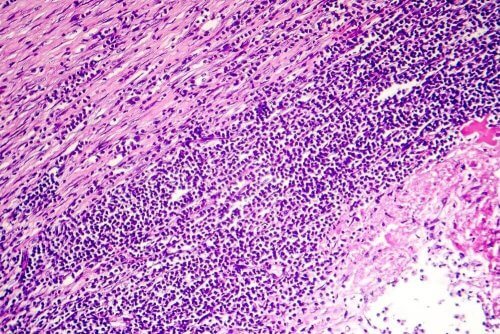

- التهاب التامور المزمن: يظهر بسبب تثخين التامور أو تراكم للسوائل. يستمر أكثر من ستة أسابيع وقد يؤدي إلى فشل البطين الأيمن. يشمل ذلك وذمة في منطقة البطن، منطقة أمام الظنبوب والكاحلين. تظهر هذه الحالة أيضًا عند تكون نسيج ليفي حول القلب، فيضغط عليه ويزيد الضغط على الأوردة التي تحمل الدم إليه. لذلك، يركد السائل التاموري ويتراكم في أجزاء مختلفة من الجسم.